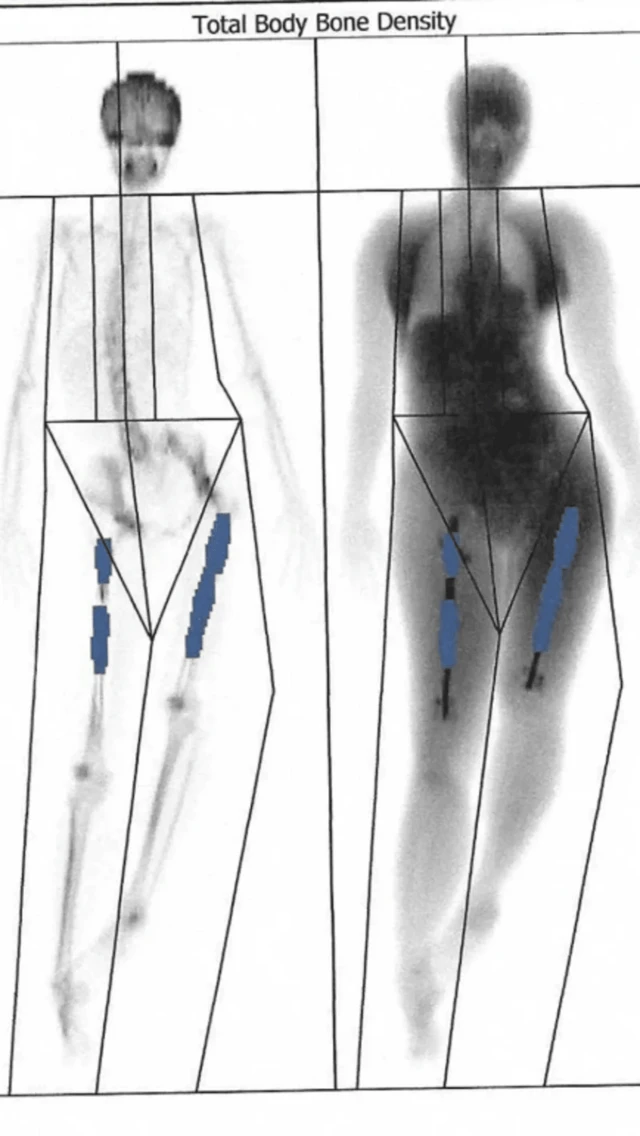

Kwa operesheni hii, maumivu fulani yanatarajiwa. Ni operesheni ambayo mifupa ya mguu imevunjwa mara mbili na fimbo ya chuma imewekwa ndani.

Fimbo za chuma huongezwa urefu hatua kwa hatua ili kuongeza urefu wa mguu na kutengenisha nusu mbili za mfupa. Mifupa iliyokatwa hupona hatua kwa hatua, ili kujaza pengo la kati.

Kufikia Septemba, mguu wake wa kulia ulikuwa umefikia lengo lake la sentimita 7. Lakini mfupa wa mguu wa kushoto wa Elaine ulionyesha ukosefu wa ukuaji. Na tofauti kati ya mguu wake wa kulia na wa kushoto ilikuwa ikisababisha matatizo, na kupindisha uti wa mgongo na kumwacha katika maumivu ya mara kwa mara.

Elaine alimgeukia Dk Guichet kwa usaidizi, ambaye alipanga upasuaji mwingine katika kliniki huko Milan. Aprili 2017, walianza tena mchakato wa kurefusha mguu wa kushoto wa Elaine huku wakiweka uboho kusaidia mfupa wa mguu wa kulia kukua. Baada ya upasuaji, Elaine aliamka na kupata habari mbaya zaidi.